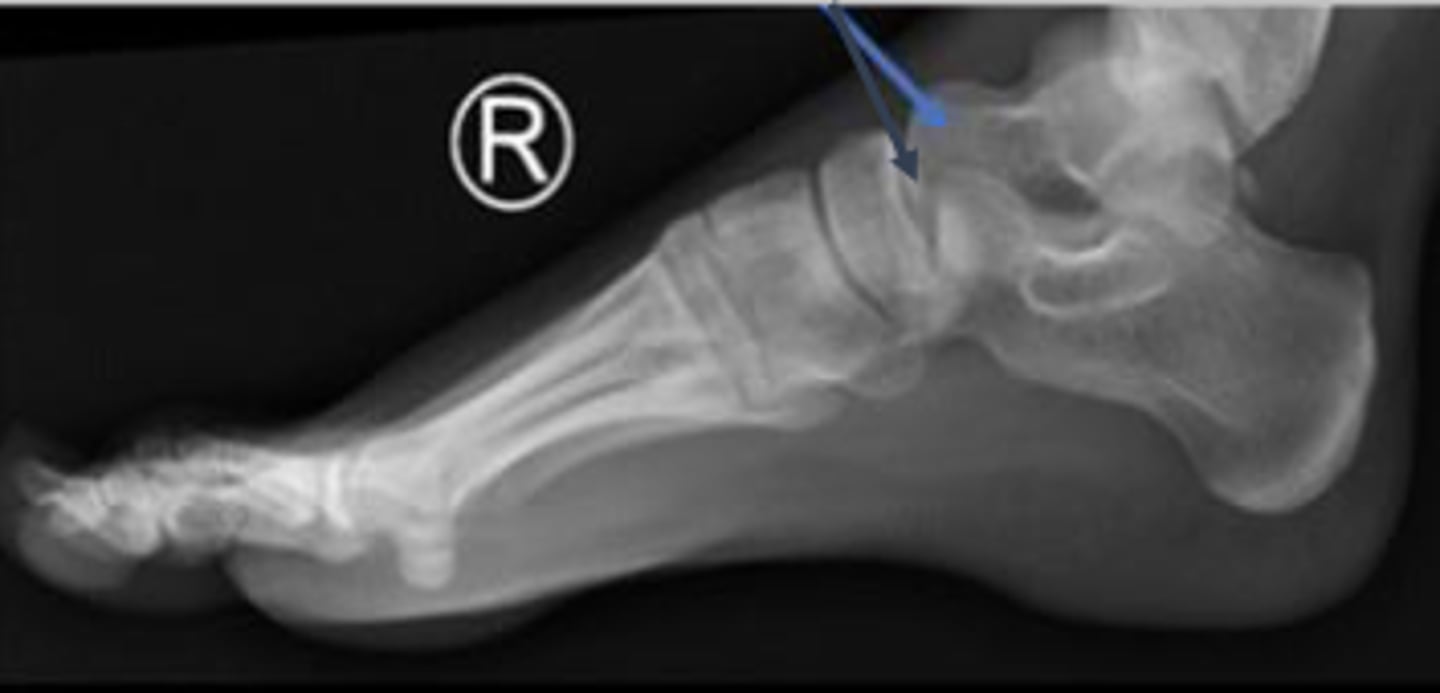

Right lateral foot

What is the name of the radiographic view?

Axial relationship of the ankle

What is the overarching name of the assessment?

Tibial angle & fibular angle

What are the 2 components of the assessment?

Tibial angle

What is the name of the assessment?

Yes

Is the assessment within normal limits?

Fibular angle

Head of the talus of the right foot

What are the arrows pointing to?

Calcaneus of the right foot